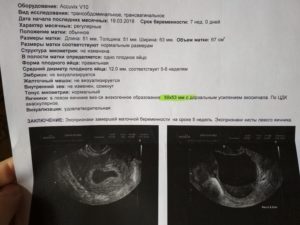

При проведении трансвагинальной эхографии (наиболее распространенный метод гинекологического УЗИ – через влагалище) при наличии маточной беременности определяется округлое анэхогенное образование – плодное яйцо 6-7 мм, расположенное в толще эндометрия.

Внутри плодного яйца визуализируются две полости, которые находятся одна в другой. Это первичный желточный мешок, а также полость внезародышевого целома. Визуализация плодного яйца возможна со срока беременности 4-5 недель.

На пятой неделе беременности эмбрион размером около 5 мм расположен около стенки желточного мешка. Желточный мешок визуализируется как кистозное образование с наличием анэхогенного содержимого. Эмбрион в желточном мешке находится эксцентрично, создавая характерную ультразвуковую картину «двойного пузыря».